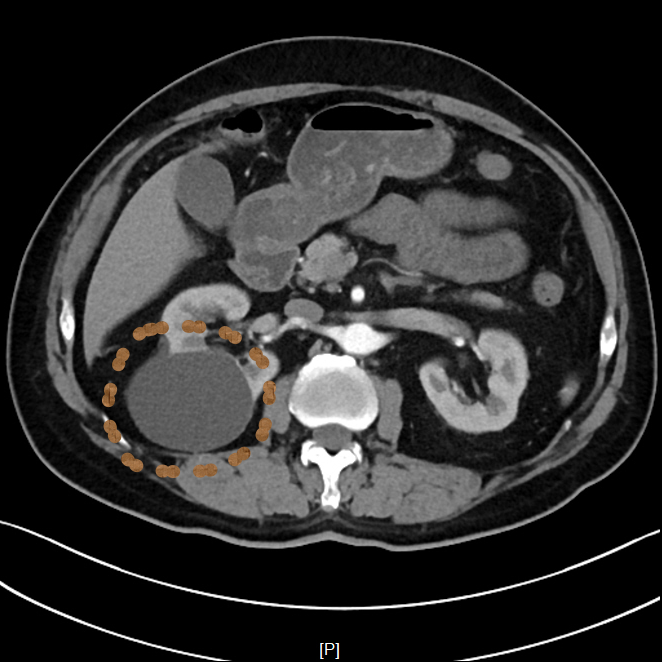

▲患者CT影像

超声介入张轶亮主治医师了解老赵的病情后立刻为其超声检查,发现右肾囊肿确实很大,已经压迫了周围肾组织。

考虑到老赵年事已高,行动不便,王晓明副主任医师当即电话联系泌尿外科,安排其住院,并行CTU(尿路造影)、血凝等术前常规检查,第二日在局部浸润麻醉下进行超声引导下肾囊肿穿刺抽液硬化治疗。

整个治疗过程不到30分钟。老赵下手术台后连连称赞现在的治疗技术真厉害,一点都没感到疼痛。术后观察24小时无明显不适即出院回家。

一个月后,老赵复查发现右肾囊肿已经缩小到1cm以内,体积缩小率高达99%老赵表示非常满意。